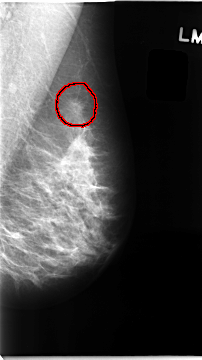

C_0097_1.LEFT_MLO

LEFT_MLO LINES 4672 PIXELS_PER_LINE 2616 BITS_PER_PIXEL 12 RESOLUTION 50 OVERLAY

FILE: C_0097_1.LEFT_MLO.OVERLAY

TOTAL_ABNORMALITIES 1

ABNORMALITY 1

LESION_TYPE MASS SHAPE IRREGULAR MARGINS SPICULATED

ASSESSMENT 5

SUBTLETY 5

PATHOLOGY MALIGNANT

TOTAL_OUTLINES 1

BOUNDARY